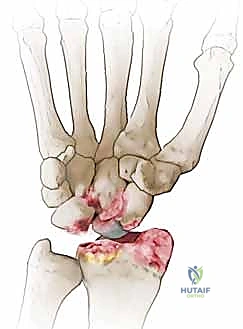

- المرحلة الأولى (Stage I): خشونة وتآكل في المفصل بين القطب البعيد للعظم الزورقي وعظم الكعبرة (الناتئ الإبري الكعبري).

- المرحلة الثانية (Stage II): يمتد التآكل والخشونة ليشمل المفصل الزورقي الكبير (Scaphocapitate joint).

- المرحلة الثالثة (Stage III): تدهور كامل يشمل المفصل بين عظم الهلالي والعظم الكبير (Capitolunate joint)، مع انهيار كامل لهيكل الرسغ.

تُعد عملية استئصال القطب البعيد للعظم الزورقي (Excision of the Distal Pole of the Scaphoid) حلاً جراحياً ذكياً ومبتكراً. الفكرة الميكانيكية وراء هذه الجراحة هي: "إذا كان القطب البعيد للعظم الزورقي هو الذي يحتك بعظم الكعبرة ويسبب الألم والخشونة، فلنقم بإزالته مع الحفاظ على باقي هياكل الرسغ".

- الاستئصال الدقيق: باستخدام أدوات جراحية ميكروسكوبية دقيقة، يتم استئصال حوالي 3 إلى 4 مليمترات من القطب البعيد للعظم الزورقي. هذه الكمية كافية لمنع الاحتكاك مع عظم الكعبرة، وفي نفس الوقت تحافظ على استقرار الأربطة.